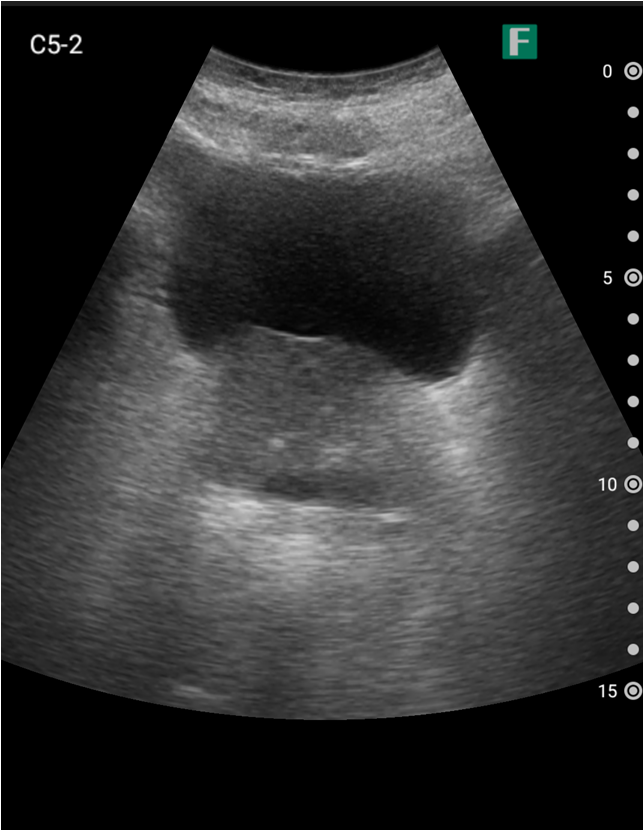

もう一つは入院患者様に対しての具体的な使用事例を紹介します。朝の回診の際にiViz airを使用し、例えば腹水のある患者様を診た際は、「今日は水の量が少なく、そこまでお腹は張ってないですね」、「今日はここに水が溜まっているんですけど、昨日より少ないですよ」など、日々の状態を患者様ご本人に伝えるようにしています。スマホで実際の画像も簡単にお見せできるので、患者様に実際に見ていただくことで少しでも不安を和らげてもらえるように心がけています。

そうして積極的に話をすると、不安そうな表情をする患者様はあまりいらっしゃらない印象を受けています。iViz airがあると患者様と会話をするきっかけにもなるため、コミュニケーションツールとしても実用的だと感じた事例でした。